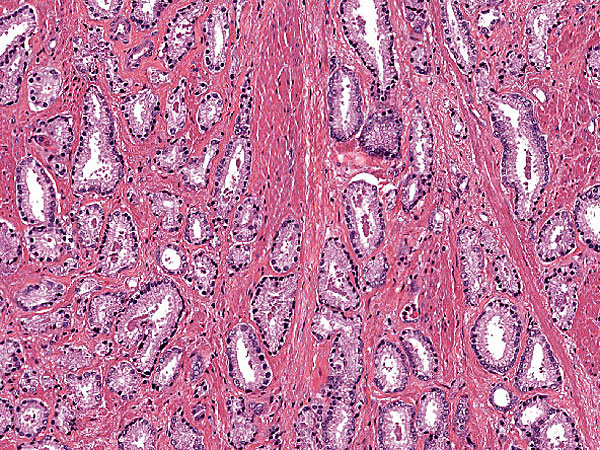

Prostatic adenocarcinoma Gleason 3